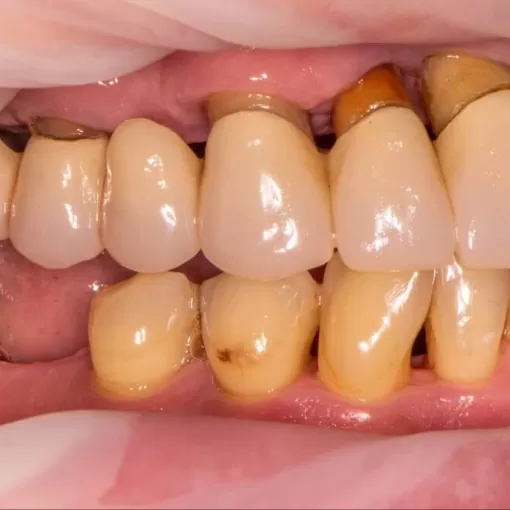

Выполнено перепротезирование коронками из диоксида циркония. Пациентка обратилась с жалобами на частичное отсутствие зубов и патологическую подвижность имеющихся зубов, диагноз частичная вторничная адентия верхней и нижней челюсти. Ей было установлено 6 имплантов по методике "все на 6" на верхней и нижней челюсти и первичный акриловый протез, через 10 месяцев выполнено перепротезирование.